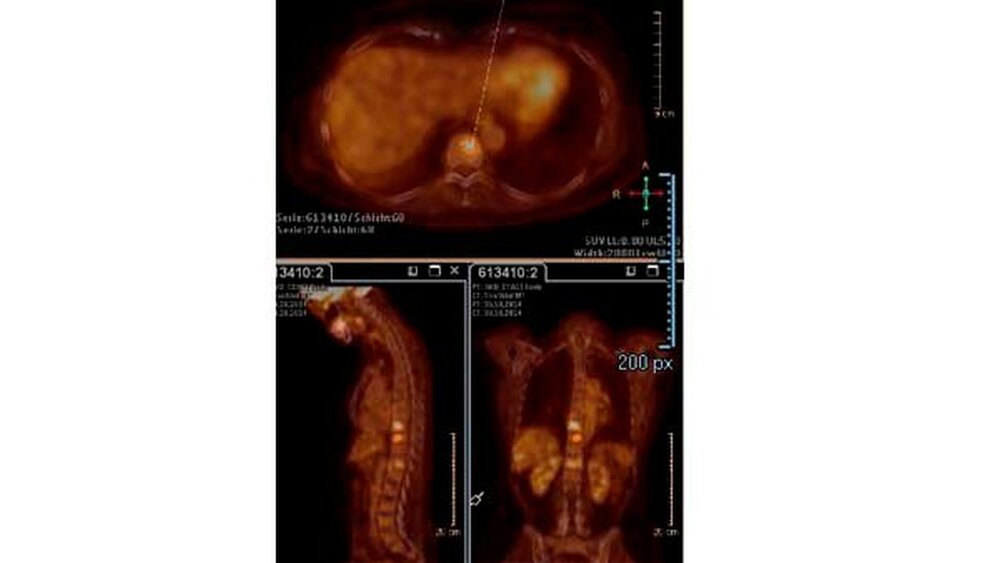

Patientin mit Knochenmetastasen

Um das weitere Wachstum und die Zerstörung im Knochen zu stoppen, waren neben der Tumortherapie die Behandlung mit hemmenden Zytostatika nötig. Das gelang ausgezeichnet, denn die ersten PET-CT Bilder stammen aus dem Jahr 2014 und die Knochenmetastasen sind seitdem nicht größer geworden.